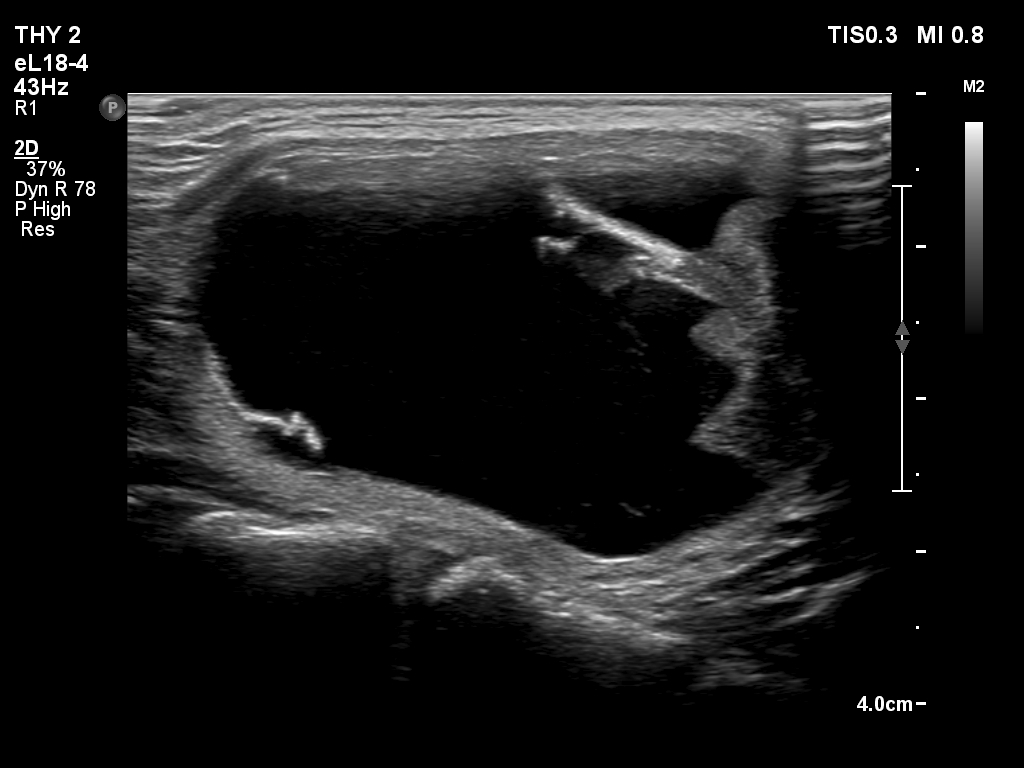

First examination (first and second rows of images):

Clinical presentation: A 25-year-old woman requested evaluation of a neck lump which was discovered by herself 3 weeks ago.

Palpation: an elastic nodule in the left lobe.

Result of blood test: TSH 1.43 mIU/L.

Ultrasonography. The thyroid was echonormal. There was a dominantly cystic nodule in the left lobe. The lesion had echonormal solid area.3.5 mL brown fluid was aspirated. The cyst has begun to refill during the aspiration of the cystic content. Cytology resulted in benign cystic lesion.